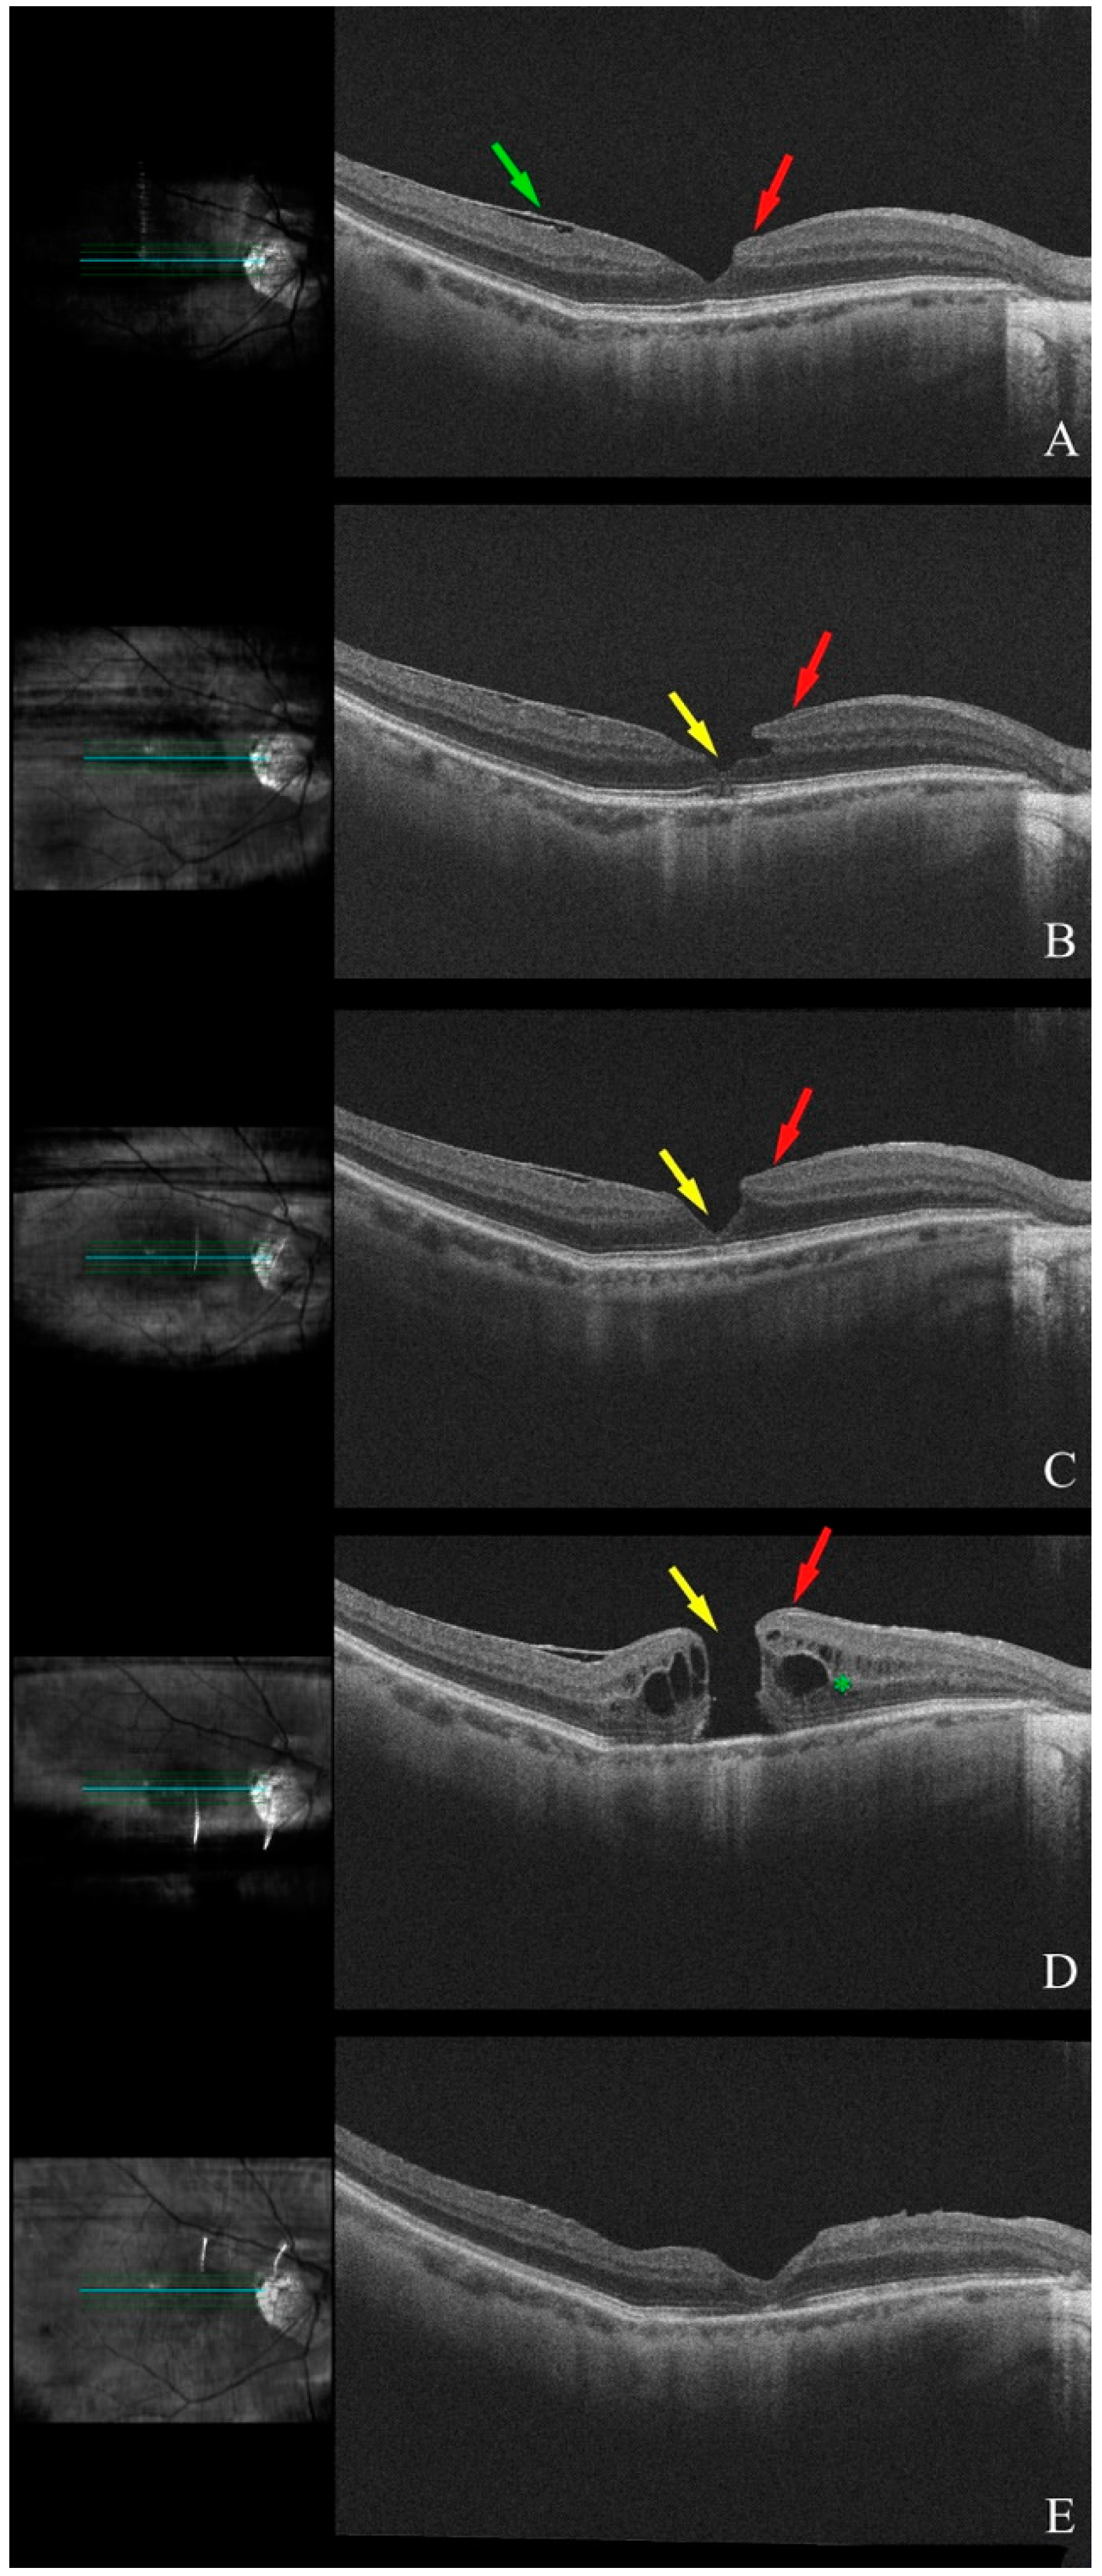

3.1.2. Patient 2, Left Eye

3.1.3. Patient 3, Left Eye

3.1.4. Patient 4, Left Eye

3.1.5. Patient 5, Right Eye

3.1.6. Patient 6, Right Eye

3.1.7. Patient 7, Right Eye

3.1.8. Patient 8, Right Eye